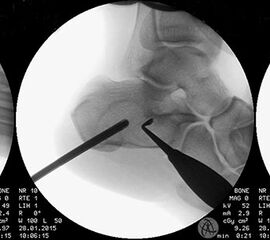

Axiale CT-Aufnahmen eines Osteoidosteoms im Bereich des Calcaneus mit typischer Nidusbildung und perifokaler Sklerose (links). Bildgesteuerte Thermofrequenzablation der Läsion (rechts).